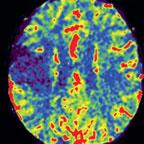

In neuroradiology, this feature assists physicians in the treatment of stroke patients by displaying a color-coded qualitative map of cerebral tissue directly in the angiography suite. syngo Neuro PBV IR further expands the Siemens imaging application portfolio for the Artis zee line of interventional X-ray systems for radiology and cardiology.

Strokes result from decreased blood flow in the brain and can cause irreparable damage to cerebral tissue. Early treatment of a stroke can help minimize damage to brain tissue. Treatment generally involves minimally invasive techniques, such as image-guided, catheter-based interventions where blood clots are either dissolved with medication or mechanically removed. syngo Neuro PBV uses cone-beam computed tomography (CT) technology to produce a qualitative colorized image similar to CT perfusion. It is designed for the visualization of contrast-enhanced blood distribution in the arterial and venous vessels in the head using color-coded relative values for diagnosis.

Parenchymal blood volume information is acquired with two C-arm rotations around the patient and a steady-state contrast injection. The system applies sophisticated processing algorithms to generate a neurological PBV map. The information is available at tableside in less than 40 seconds without the need for any further user interaction.